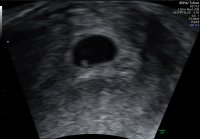

Jeg var ca 5+6 første gangen når hun så bare plommesekken. I dag skal jeg være ca 6+6, hun målte ca 6+4 som hun sa var bra. Og at jeg muligens er ca 6+4/6+5, men kan også være 6+6. Utstyrer er ikke tipp topp, men helt greit.Så deilig utfall

Hva ble du målt til å være? Jeg skal når jeg er 5+6 og er egentlig litt redd for å ikke se noe. Skal uken etter også, men vil så gjerne så tidlig som mulig.